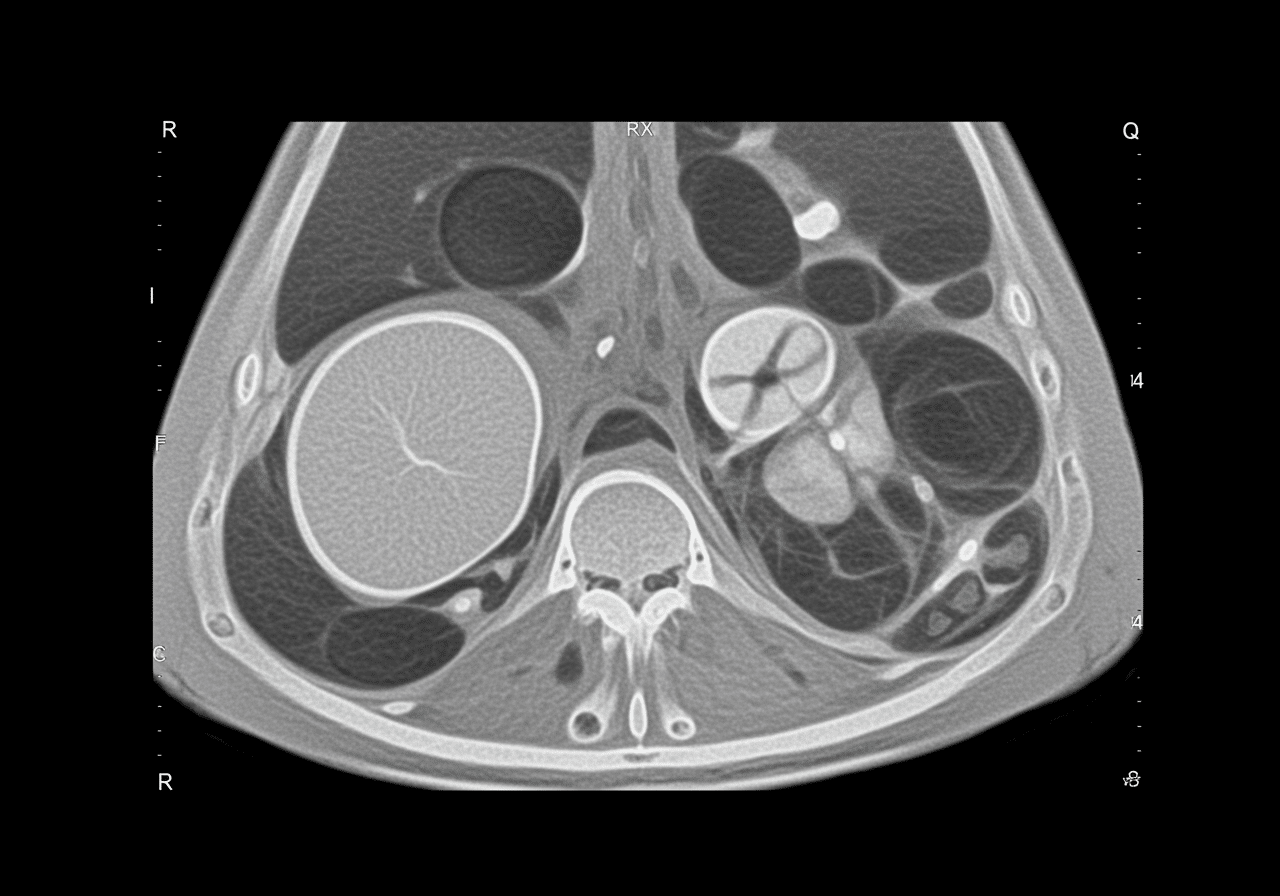

Can abdominal CT detect internal bleeding from trauma?

Yes, contrast-enhanced abdominal CT detects internal bleeding with 98% sensitivity, identifying solid organ injuries (liver, spleen, kidney lacerations), active arterial bleeding appearing as contrast "blush" or extravasation, and bowel or mesenteric injuries. Priority ER emergency physicians use AAST organ injury scales grading injury severity determining conservative management with serial hemoglobin checks versus immediate surgery or angioembolization. Free fluid without solid organ injury suggests bowel perforation or mesenteric injury requiring emergency exploratory laparotomy preventing peritonitis and sepsis from delayed diagnosis.

Priority ER's diagnostic capabilities for abdominal CT for suspected appendicitis, perforation, or internal bleeding exceed Joint Commission standards for emergency departments[14], featuring 64-slice multidetector CT scanner providing immediate high-resolution abdominal imaging with arterial, portal venous, and delayed phases identifying appendicitis (sensitivity 95%, specificity 94%), bowel perforation showing extraluminal air or oral contrast, and active arterial bleeding appearing as contrast extravasation requiring angioembolization[15]. Our emergency physicians trained in abdominal CT interpretation identify McBurney's point tenderness correlating with CT findings, periappendiceal fat stranding indicating inflammation, appendicolith suggesting obstruction, and appendiceal diameter >6mm confirming appendicitis requiring surgical consultation within hours preventing perforation.

Advanced imaging through our comprehensive diagnostic capabilities provides CT enterography protocols for small bowel evaluation, rectal contrast administration when pelvic abscess or appendiceal perforation suspected, and immediate interventional radiology consultation when CT identifies active arterial extravasation requiring angiography and coil embolization as alternative to surgery. For trauma patients, our emergency physicians utilize American Association for Surgery of Trauma (AAST) organ injury grading scales determining which solid organ injuries require operative management versus nonoperative observation with serial imaging and hemoglobin monitoring. This comprehensive approach explains why the American College of Radiology appropriateness criteria mandate CT as first-line imaging for suspected appendicitis in adults, replacing ultrasound and clinical diagnosis alone improving diagnostic accuracy from 80% to 98%.